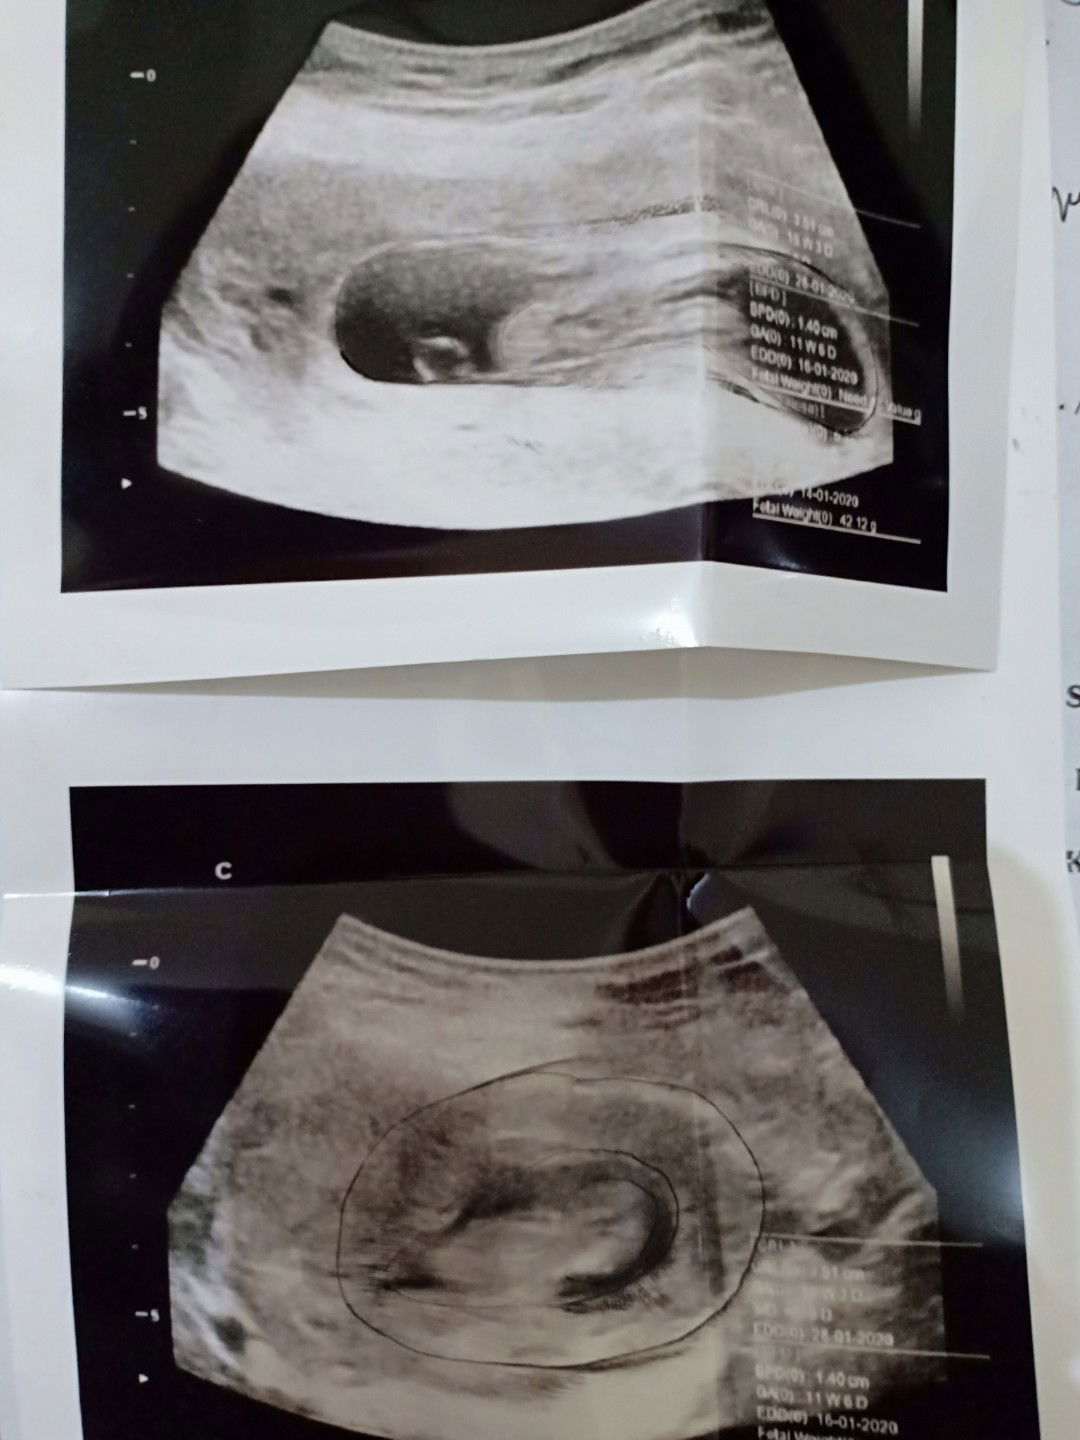

USG

Alhmdllh smua nya normal dan janin nya sehat..???

Usia 11 w 6 d....gak jelas...di kertas ada tulisanne

Alhamdulillah.... Usia brp bulan itu bun?

11mggu bun 😊

btw itu brp minggu bun?

11mggu bun